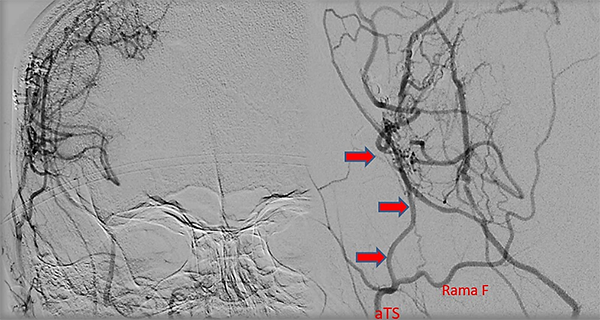

Caso clínico #1: PR masculino de 20 años sin antecedentes clínicos, estudiado por cefaleas de varios meses de evolución. La RMN no presenta lesiones y la ARM evidencia una disminución del flujo de la arteria cerebral media derecha. La ADC muestra la estenosis progresiva de la arteria carótida interna derecha supraclinoidea, ausencia de opacificación del origen de la arteria cerebral media y anterior, presencia de vasos de MM con escasa circulación colateral desde carótida interna izquierda a través de la comunicante anterior; corresponde a un grado 3 de Suzuki (Fig. 1). Se realizó una revascularización cerebral combinada: un bpTS más EDMS derecho, la evolución postoperatoria fue sin complicaciones y la ADC diferida muestra una buena perfusión cerebral a través del bypass y la sinangiosis (Fig. 2). El control clínico a 4 años es favorable y las imágenes de RMN y RMA evidencian ausencia de nuevas lesiones isquémicas y adecuada revascularización.

Fig. 1 Caso clínico #1. ARM y ADC preoperatoria, obsérvese la estenosis progresiva de la arteria carótida supraclinoidea derecha con ausencia del origen de las arterias cerebral anterior y media. Corresponde a un grado 3 de Suzuki

Fig. 2 Caso clínico #1. ADC postoperatoria en frente (izquierda) y perfil ampliado (derecha), bp TS derecho con un buen calibre en la arteria temporal superficial (aTS) y muy buena perfusión cerebral